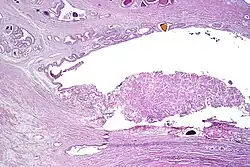

Pseudohyperplastic carcinoma 2%[5] 11%[5]

• Large-sized or dilated glands[1]

• Branching and papillary infolding[1]

• Tall columnar cells[1]

• Abundant pale to slight granular luminal cytoplasm[1]

• Nuclei towards basement membrane[1]

Tumorous glands:

• 34βE12- and p63- [1]

• AMACR+ in 70–83% of cases[1]

3+3=6[1]